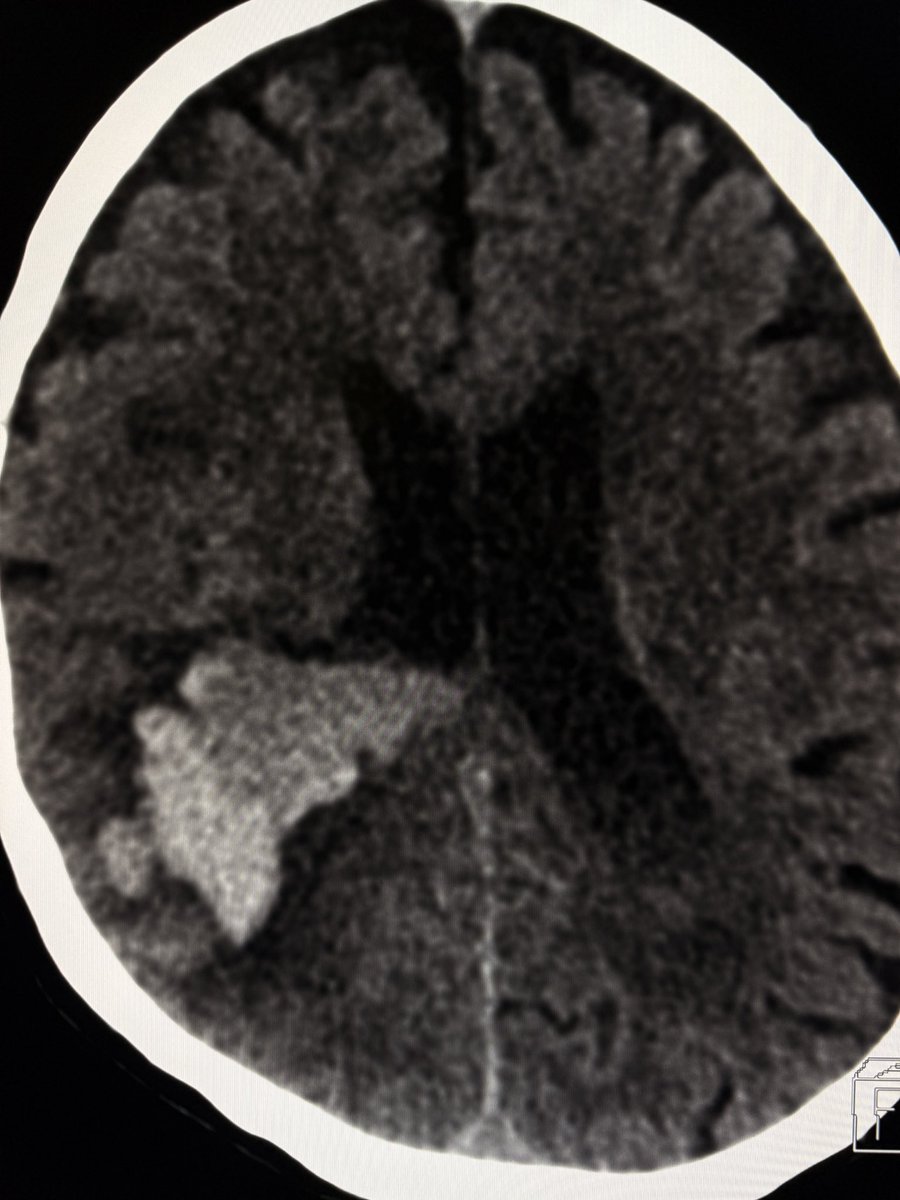

Layering or hematocrit level or differential density within an acute intraparenchymal bleed on CT? Think: 1. coagulopathy 2. anticoagulants 3. Tumor-related bleed 4. evolving /expanding hematoma with active bleed. —On-call pearls from my reporting list

Layering or hematocrit level or differential density within an acute intraparenchymal bleed on CT?

Think: 1. coagulopathy  2. anticoagulants 3. Tumor-related bleed 4. evolving /expanding hematoma with active bleed.

—On-call pearls from my reporting list